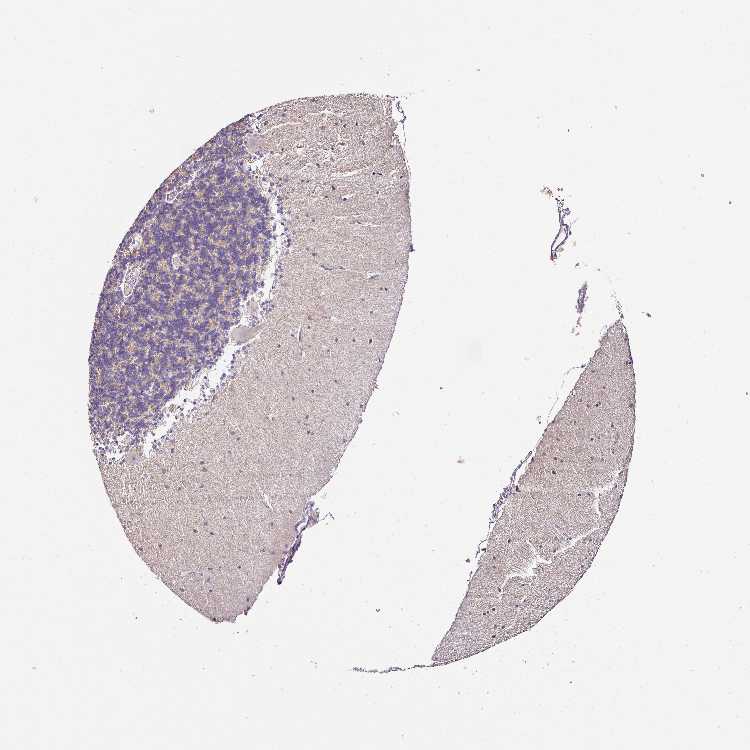

CEREBELLUM - Antibody stainingi

Antibody staining in the annotated cell types in the current human tissue is reported as not detected, low, medium, or high, based on conventional immunohistochemistry profiling in selected tissues. This score is based on the combination of the staining intensity and fraction of stained cells.

Each image is clickable and will lead to virtual microscopy that enables deeper exploration of all samples and also displays staining intensity scores, fraction scores and subcellular localization as well as patient and tissue information for each sample.

Antibody HPA045280Antibody HPA047236Antibody HPA047744Antibody CAB009591

Purkinje cells Not detectedNot detectedNot detectedNot detected

Cells in granular layer Not detectedNot detectedNot detectedNot detected

Cells in molecular layer Not detectedNot detectedNot detectedNot detected